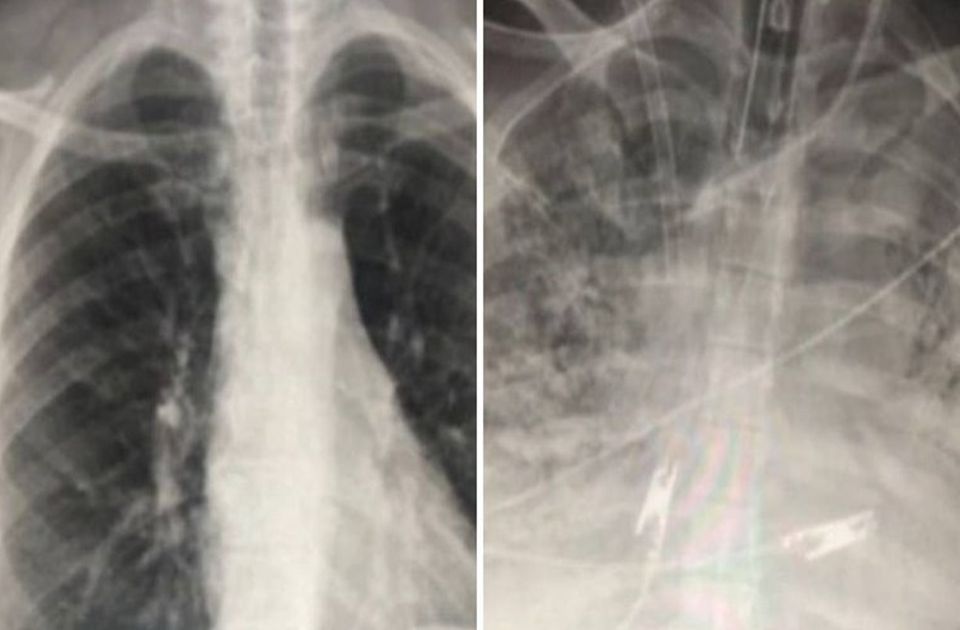

Ahogyan 2022-ben, úgy 2050-ben is a tüdőrák lesz az előrejelzések szerint a rákos megbetegedések és a rákos halálozások vezető oka a férfiak körében. A legnagyobb növekedést pedig a megbetegedések terén a mesothelioma (a mellhártya rossz indulatú daganata, amely leginkább az azbesztszennyezésre vezethető vissza), a halálozások terén pedig a prosztatarák terén jelzik előre a kutatók. De ugyanígy növekedést várnak az adatok alapján a hólyagrák és a bőrrák okozta halálozások esetében is.